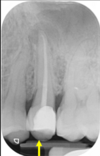

Q

what is this superimposition?

A

maxillary antrum